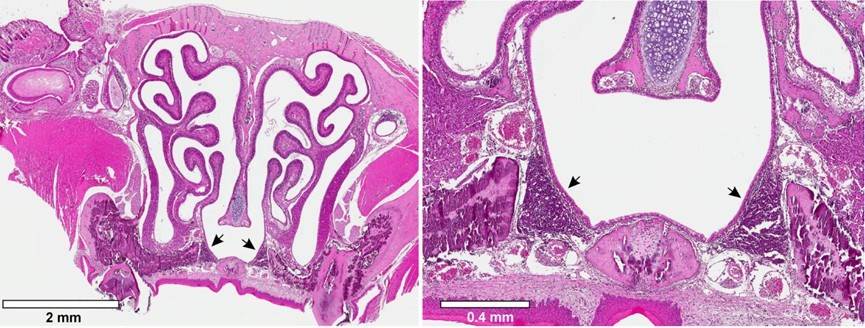

Mouse nasal cross section associated lymphoid tissue.Fig 1. Nasal-associated lymphoid tissue.1

1. Gogos, Artemis, and Michael J Federle. "Modeling Streptococcus pyogenes Pharyngeal Colonization in the Mouse." Frontiers in cellular and infection microbiology 9,137 (2019): 2. Distributed under Open Access license CC BY 4.0, without modification.